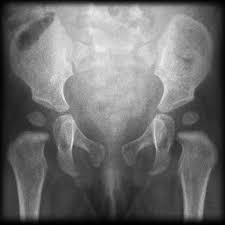

Pelvic X Ray Different Ages Radiology Case Radiopaedia Org

Does This Child Have Precocious Puberty Paediatricfoam